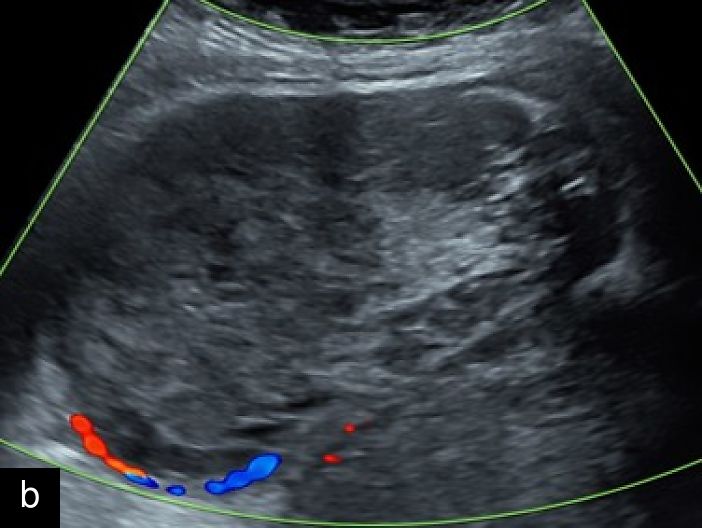

3

Transvaginal (a) and transabdominal (b) ultrasound images of uterine sarcoma. The lesion exhibits heterogeneous echotexture, irregular margins and peripheral vascularity on color Doppler. While uterine sarcomas are often highly vascularized, cases with lower vascularization can pose challenges in the differential diagnosis from benign myometrial lesions, such as atypical leiomyomas.